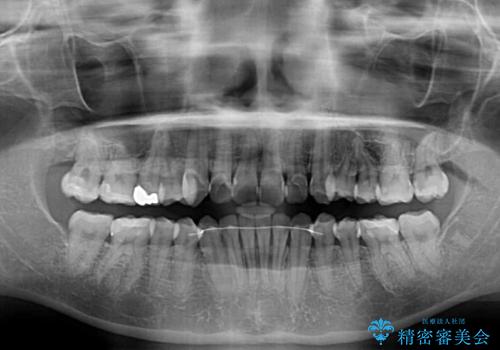

デコボコ歯列をきれいに インビザラインによる矯正治療

- 上下歯列全体のデコボコを気にして来院された患者様です。

主に下顎歯列全体の後方移動とIPR(歯と歯の間を削る)によってデコボコが解消するように設計し、インビザラインにより治療を行うこととしました。

奥歯の知覚過敏が顕著となり、その影響で奥歯の咬み合わせ改善のための顎間ゴムの装着ができず、咬合を仕上げるまでに長い期間を要することとなりました。